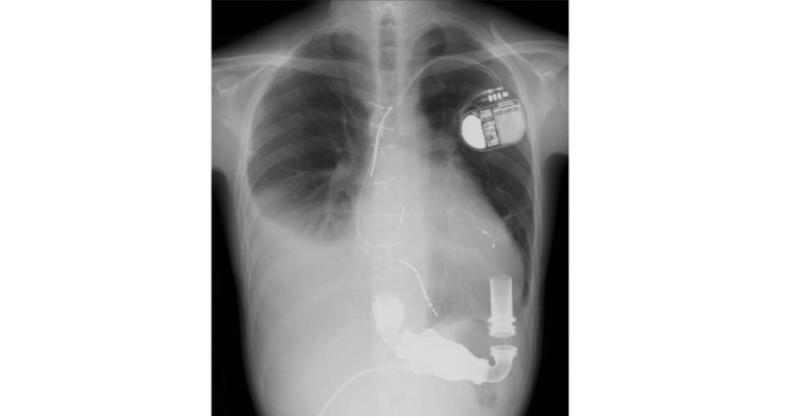

- Right Heart Failure after Left Ventricular Assist Device Implantation in a 30-Year-old Man

Right heart failure (RHF) after left ventricular assist device (LVAD) implantation is an extremely critical issue. When the presence of RHF is evident preoperatively, nitric oxide inhalation and/or inotropic administration is administered over a long period after LVAD implantation. Extremely severe cases need the right ventricular assist device (RV